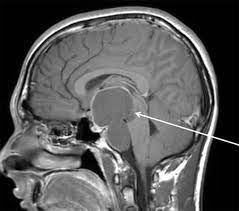

Внутричерепная опухоль локализуется в селлярной или параселлярной области головного мозга, состоит из эпителиальной ткани, формируясь из эмбриональных клеток. Врожденное образование характеризуется медленным ростом и низкой степенью малигнизации. Несмотря на доброкачественность, несет определенную угрозу здоровью ребенка, вследствие анатомических особенностей локализации. Из-за близости краниофарингиомы к гипофизу, зрительному нерву, гипоталамусу вызывает серьезные осложнения и затруднения в хирургическом лечении, влияет на эндокринные функции. Краниофарингиома представляет собой образование плотной структуры, состоящей из кист, заполненных жидкостью. Причины возникновения опухоли доподлинно неизвестны, но предположительно провоцирующими факторами называют нарушения внутриутробного развития и генетическую предрасположенность.